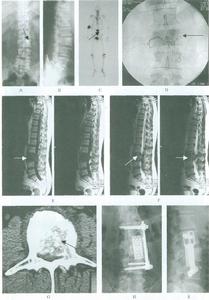

2、B型超聲檢查示子宮增大,宮腔內有液性暗區,內有強光點。

宮頸癌合併宮腔積膿一般沒有特異的臨床表現。超聲表現為子宮體增大,宮腔內充滿液性暗區,暗區內散在疏密程度不等的點狀回聲,積膿較重時肌層受壓變薄。宮頸可表現為正常回聲、不均質回聲或出現異常結節。

超聲對於宮腔積膿的診斷較容易,而要確定是否為宮頸癌所致則較難,在以下情況下應考慮宮頸癌合併宮腔積膿的診斷:(1)老年患者出現宮腔積膿;(2)宮腔積膿而宮體內膜均勻且不增厚;(3)宮腔積膿合併宮頸部回聲異常。

宮頸癌並宮腔積膿應注意與子宮內膜癌合併宮腔積膿鑑別。子宮內膜癌患者多有絕經後陰道出血和陰道排液;聲像圖除宮腔積膿外還表現為子宮內膜瀰漫性不均勻增厚(可達0.6cm以上),或呈團塊狀,子宮肌層常有浸潤,出現不規則異常回聲。患者術前可能被誤診為盆腔囊腫,這是因為子宮體完全失去正常回聲而呈薄壁樣囊性腫塊,此病例提醒我們當老年人發現盆腔內囊性腫塊時應考慮到宮腔積膿的可能性,此時應仔細觀察子宮的情況及與囊性腫塊的關係,以免誤診。

宮腔積膿掃描圖資料與方法

一般資料:患者10例,年齡49~79歲,平均65歲。絕經年限8~27年,平均18年,均為自然絕經。10例患者中,有慢性盆腔炎病史者5例,有高血壓病史者2例,合併糖尿病者3例。

臨床表現:10例患者中,均有程度不同的下腹墜脹、隱痛不適。5例合併尿頻或排尿困難,同時伴發熱。7例患者能查出盆腔腫物,腫物呈囊性或囊實性,境界較清,有程度不等的壓痛。用探針探查宮腔,探針通過宮口時可感到阻力,探入後有膿汁從宮口流出。餘3例因腹壁過厚或其他原因未能查清盆腔的異常改變。另有老年性陰道炎者9例,子宮脫垂1例。

輔助檢查:超聲提示宮腔積液者7例,疑為卵巢腫物者2例,盆腔膿性(子宮外)包塊者1例。血常規提示白細胞升高者5例,尿常規提示合併尿路感染者5例。宮腔診刮及宮腔吸片後病理檢查顯示子宮內膜癌者1例。